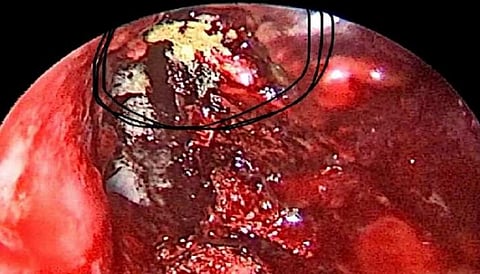

இந்த தகவல் இந்தியா முழுவதும் கடும் பீதியை ஏற்படுத்தியது. மேலும் இதற்கான மருந்துகளை வெளிநாடுகளில் இருந்து வாங்க இந்திய அரசு முடிவு செய்துள்ளது. இந்நிலையில் உத்தரப்பிரதேசத்தின் காஜியாபாத் சஞ்சைநகரை சேர்ந்த இளைஞர் ஒருவருக்கு 3 வித பூஞ்சை தொற்றும் ஏற்பட்டுள்ளது கண்டுபிடிக்கப்பட்டது.

அதாவது அந்த நபரின் உடலில் கருப்பு,வெள்ளை,மஞ்சள் என மூன்று விதமான பூஞ்சை தொற்றுகளும் கண்டறியப்பட்டுள்ளது. இது குறித்து தெரிவித்துள்ள மருத்துவர் ஒருவர், ஒருவருக்கு மூன்று விதமான பூஞ்சை தொற்றும் பரவியிருப்பது கண்டறியப்பட்டுள்ளது நாட்டிலேயே இது தான் முதல் முறை என தெரிவித்துள்ளார்.